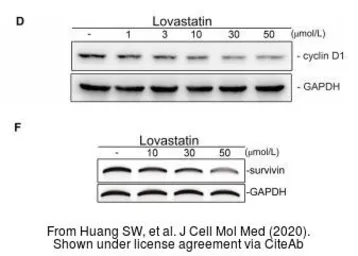

The data was published in the journal J Cell Mol Med in 2020. PMID: 31821701

The data was published in the journal J Cell Mol Med in 2020. PMID: 31821701